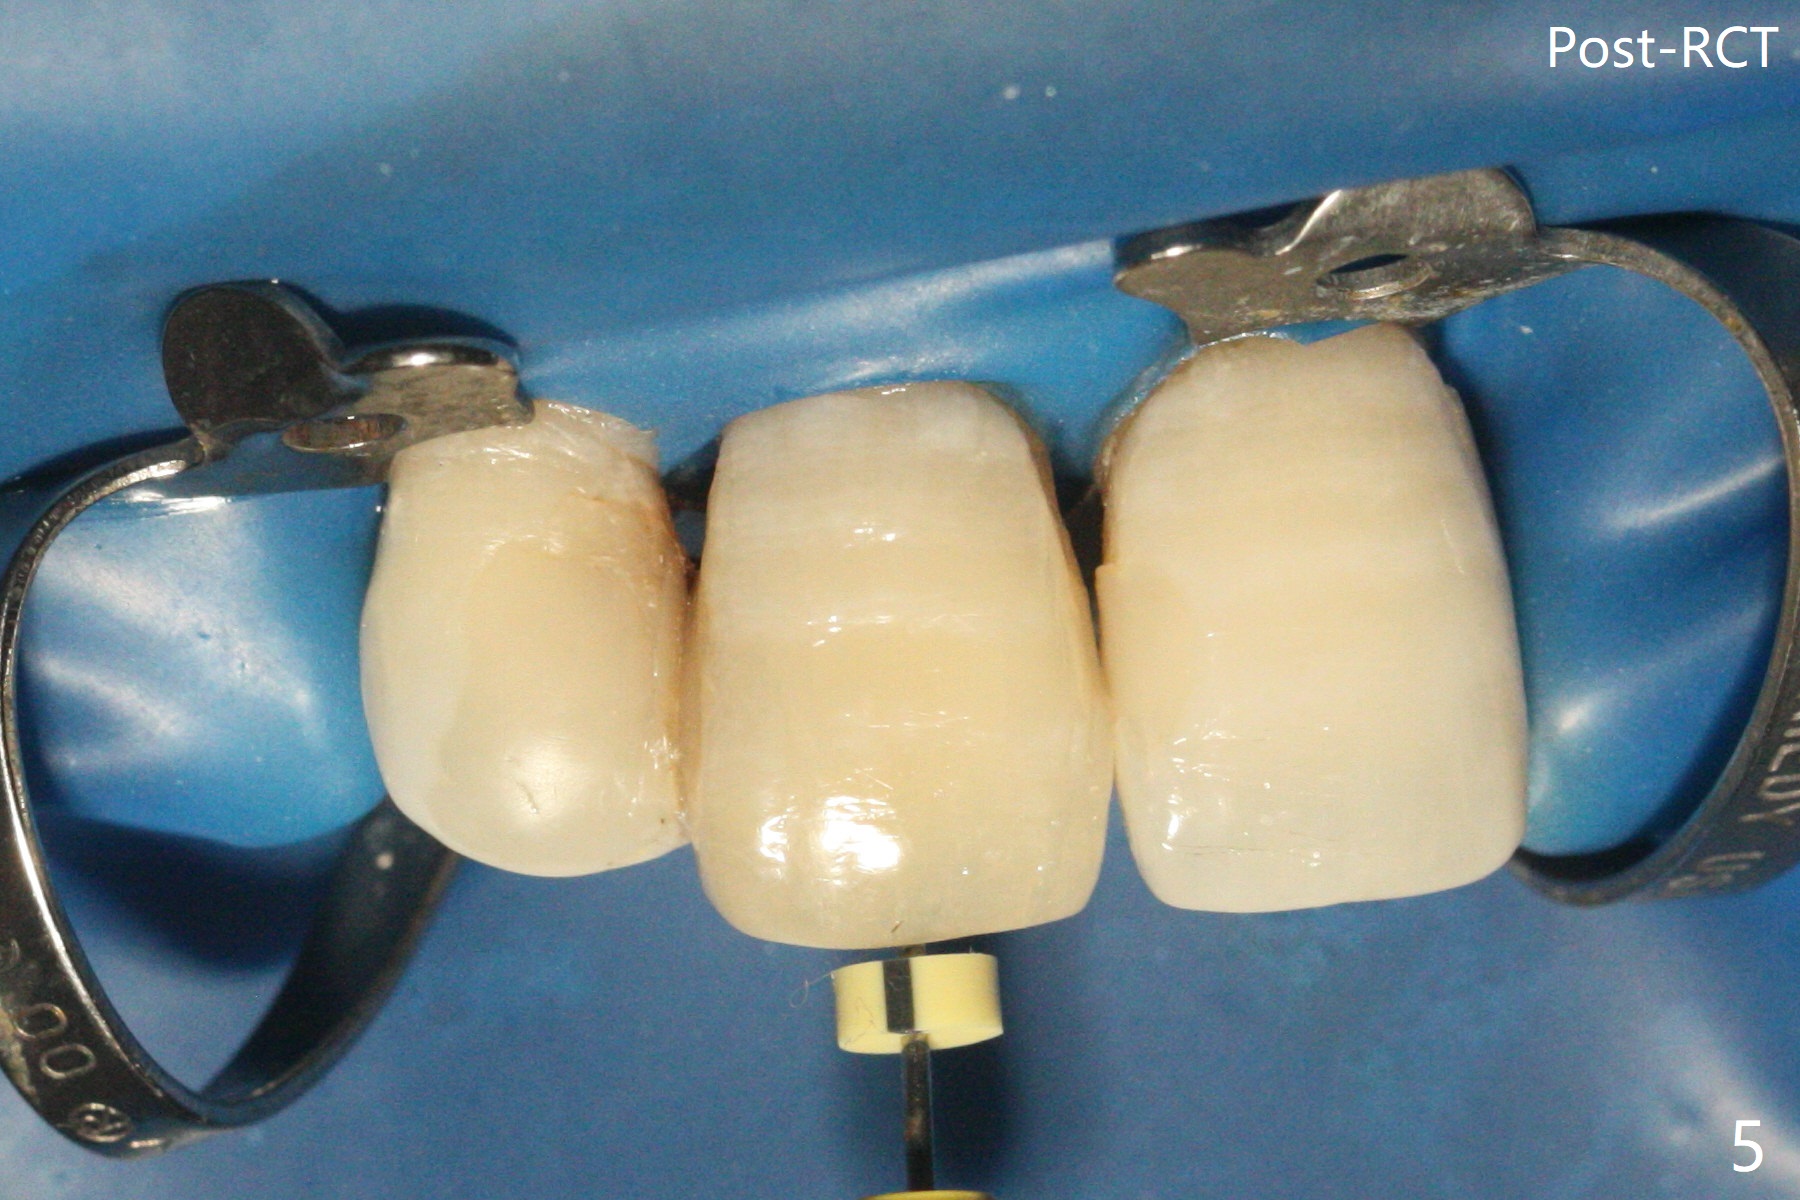

单个门牙变色往往是牙髓坏死所致,根管充填后做漂白,防止漂白泡沫跑到根尖孔之外,这种顺序可以改变吗?53岁女右上1根尖无痛性红肿(图一:^),牙冠变色(图二),牙髓测定:死髓,伴有根尖阴影(图三),中切牙需要根管治疗,什么时候漂白最好,步骤便利?根管治疗后做内漂白,必须把牙胶尖取出,釉牙骨质交界处之下,牙冠长,如这个病例,取出可能困难。我们准备尝试根管治疗当中做漂白,由于死髓牙,根管治疗可以不需要局麻,三个牙齿暴露在橡皮障之外(图四),以便术中漂白观察。根管治疗当中使用大量漂白水,好象并没有改善颜色(图五)。所以在根管口(图六)注入35%双氧水(漂白液,胶状),适当超越釉牙骨质交界处。万一双氧水气泡跑出根尖孔,我们将用生理盐水冲洗,不过这个意外没发生。双氧水也放置在患牙表面(外漂白),两次漂白后(每次20分钟),病人满意牙冠颜色改变(图七)。冲洗,擦干后,在根管中放置氢氧化钙糊剂。预约一个月后完成根管充填,如果牙冠颜色反弹,再次漂白。充填前需要多次冲洗,清除残余双氧水,后者抑制树脂固化。